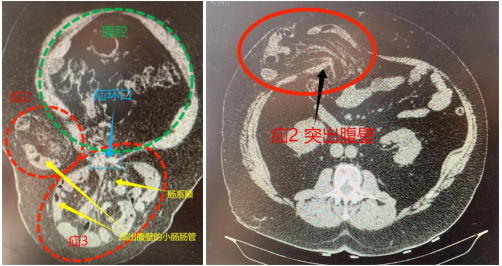

近期开展的疑难手术如下(文末有详细链接查看):外国友人多发巨大切口疝腔镜复合补片修补术(图1-3)、强直性脊柱炎患者腹股沟疝腹腔镜无张力疝修补术(TAPP)(图4)、复发性造瘘口旁疝杂交疝修补术、疑难巨大嵌顿脐疝腹腔镜腹膜外无张力疝修补术(TEP)、反流性食管炎合并食管裂孔疝补片修补并胃底折叠术、小儿疝单孔腹腔镜疝囊高位结扎术等。

图4